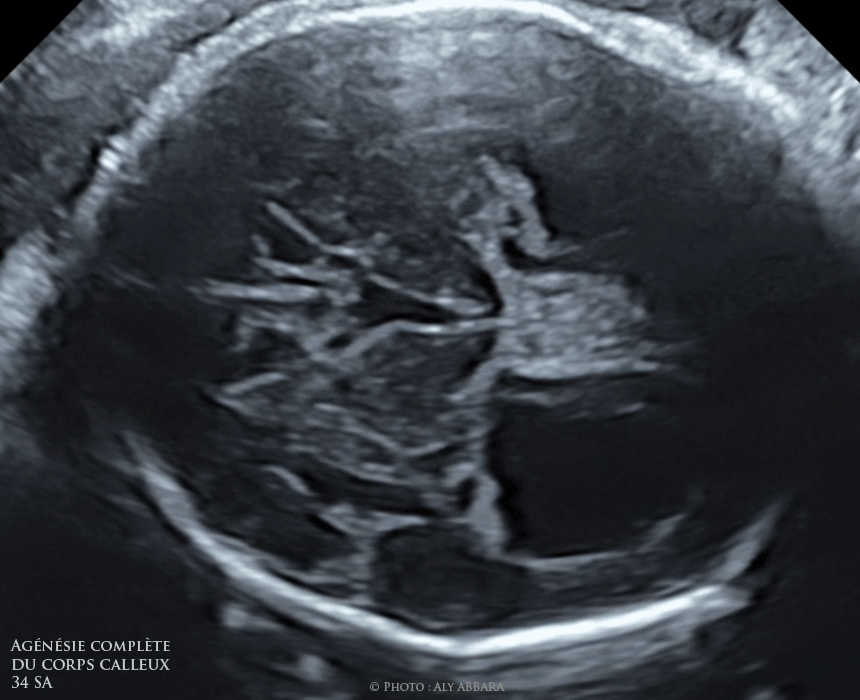

Agénésie complète du corps calleux - Dilatation du 3ème ventricule et absence du cavum du septum pellucidum

Images et séquences vidéo échographique montrant la présence d'une agénésie complète du corps calleux chez un foetus âgé de 34 SA.

On identifie sur ces images :

• L'absence du cavum du septum pellicidum.

• La dilatation du troisième ventricule

• La dilatation de les cornes postérieures des ventricules latéraux (colpocéphalie)